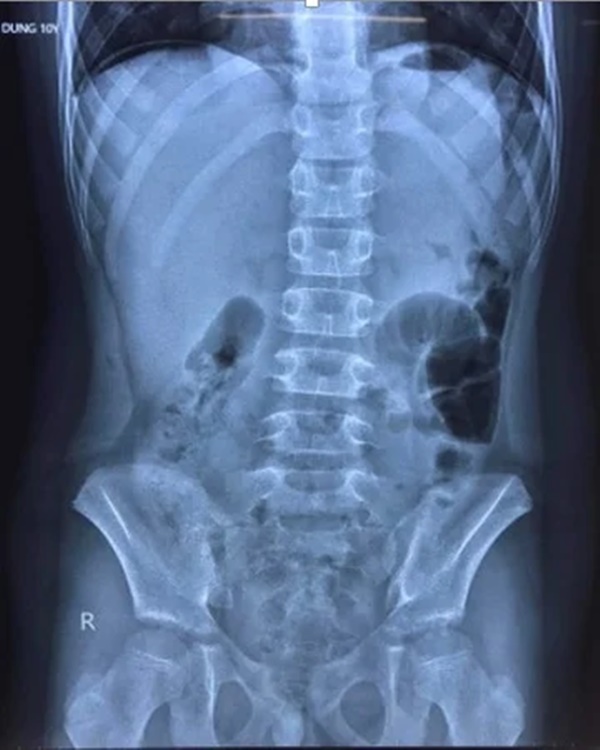

Hình ảnh chụp X-quang cho thấy bệnh nhi có liềm hơi dưới vòm hoành 2 bên, bác sĩ nghi thủng tạng rỗng. Ảnh: Bệnh viện Trẻ em Hải Phòng cung cấp.

Theo hình ảnh chụp X-quang, bệnh nhi có liềm hơi dưới vòm hoành 2 bên. Tại Bệnh viện Trẻ em, bé được chẩn đoán bị viêm phúc mạc do thủng dạ dày/mắc Covid-19.